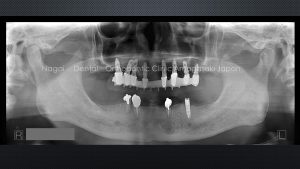

70代男性。歯抜けが止まらない原因に迫る

どんどん歯が抜けてしまった患者さんのお話です。3年の間に歯がどんどん抜けていき、部分入れ歯が大きくなっているのがわかります。

上の奥歯と下の前歯がぐらぐらになって抜けてきました

ご本人は、「ちょっとずつ抜けていっているから、あと2年はもつと思います」とおっしゃっていましたが、お話しているうちに、いまのうち根本的に治療したいということになり、上の歯は当時力を入れていたAGCブリッジ、下はズレない入れ歯で、入歯がズレるのを防ぐために天然の歯3本にスナップをつけて、左にインプラント1本だけ入れることにしました。

なぜ歯がどんどん抜けてしまったのか? 原因は噛み合わせと歯周病だと考えられました。

この方は、向かって真ん中右隣の歯が伸びてきていました。上下の歯の咬み合わせが深く、あごが横に動いたときに上下が逃げない、奥歯が離れない咬み合わせになっていました。そうした点を改善し、お口全体の噛み合わせを整えました。

上顎のインプラントは本数が6本以上で強度が出るのでブリッジの形でしっかり力を受け止める設計にしました。一方、下の歯は入れ歯の形にしました。インプラントと天然の歯の本数から考えて下には強い力がかからないようにしました。天然と入れ歯に、またインプラントと入歯の間には重心を下げた低い位置にスナップを、入れ歯がズレないようにしています。重心が低いと歯にかかる横向きの力が少なくなり、歯とインプラントと入れ歯が長持ちしやすいように工夫しています。

咬み合わせ以外にもう1つ、歯が抜ける原因となっていた歯周病も、インプラントを入れる前のタイミングでしっかり除菌しました。咬み合わせと歯周病を改善し、残りの歯を守る治療ができました。